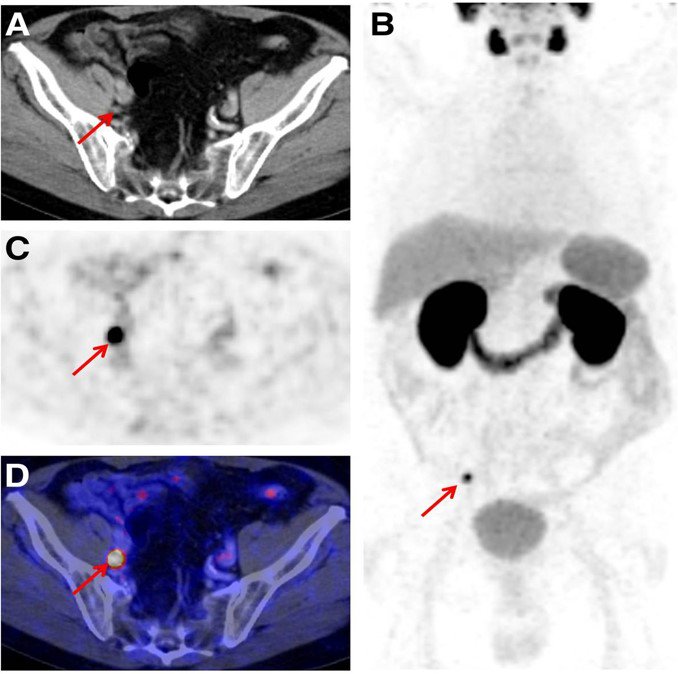

#MRI for new insights into posterior fossa tumours in children. Brilliant work from our collaborators Sotirios Bisdas and Felice D'Arco #cancerresearch #imaging lnkd.in/eGm--t6

#Breastcancer in #2020 - what is the future of #radiology ? AuntMinnieEurope #rsna16 #PrecisionMedicine #rkr16 #mri auntminnieeurope.com/index.aspx?sec…

#Brain #cancer: New #biomarker could improve #diagnosis of #glioma! #Neuroimaging #Cancer #Research medicalnewstoday.com/articles/31458… /via Medical News Today